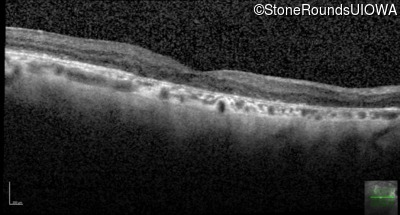

Age at visit: 55 years

OD OS